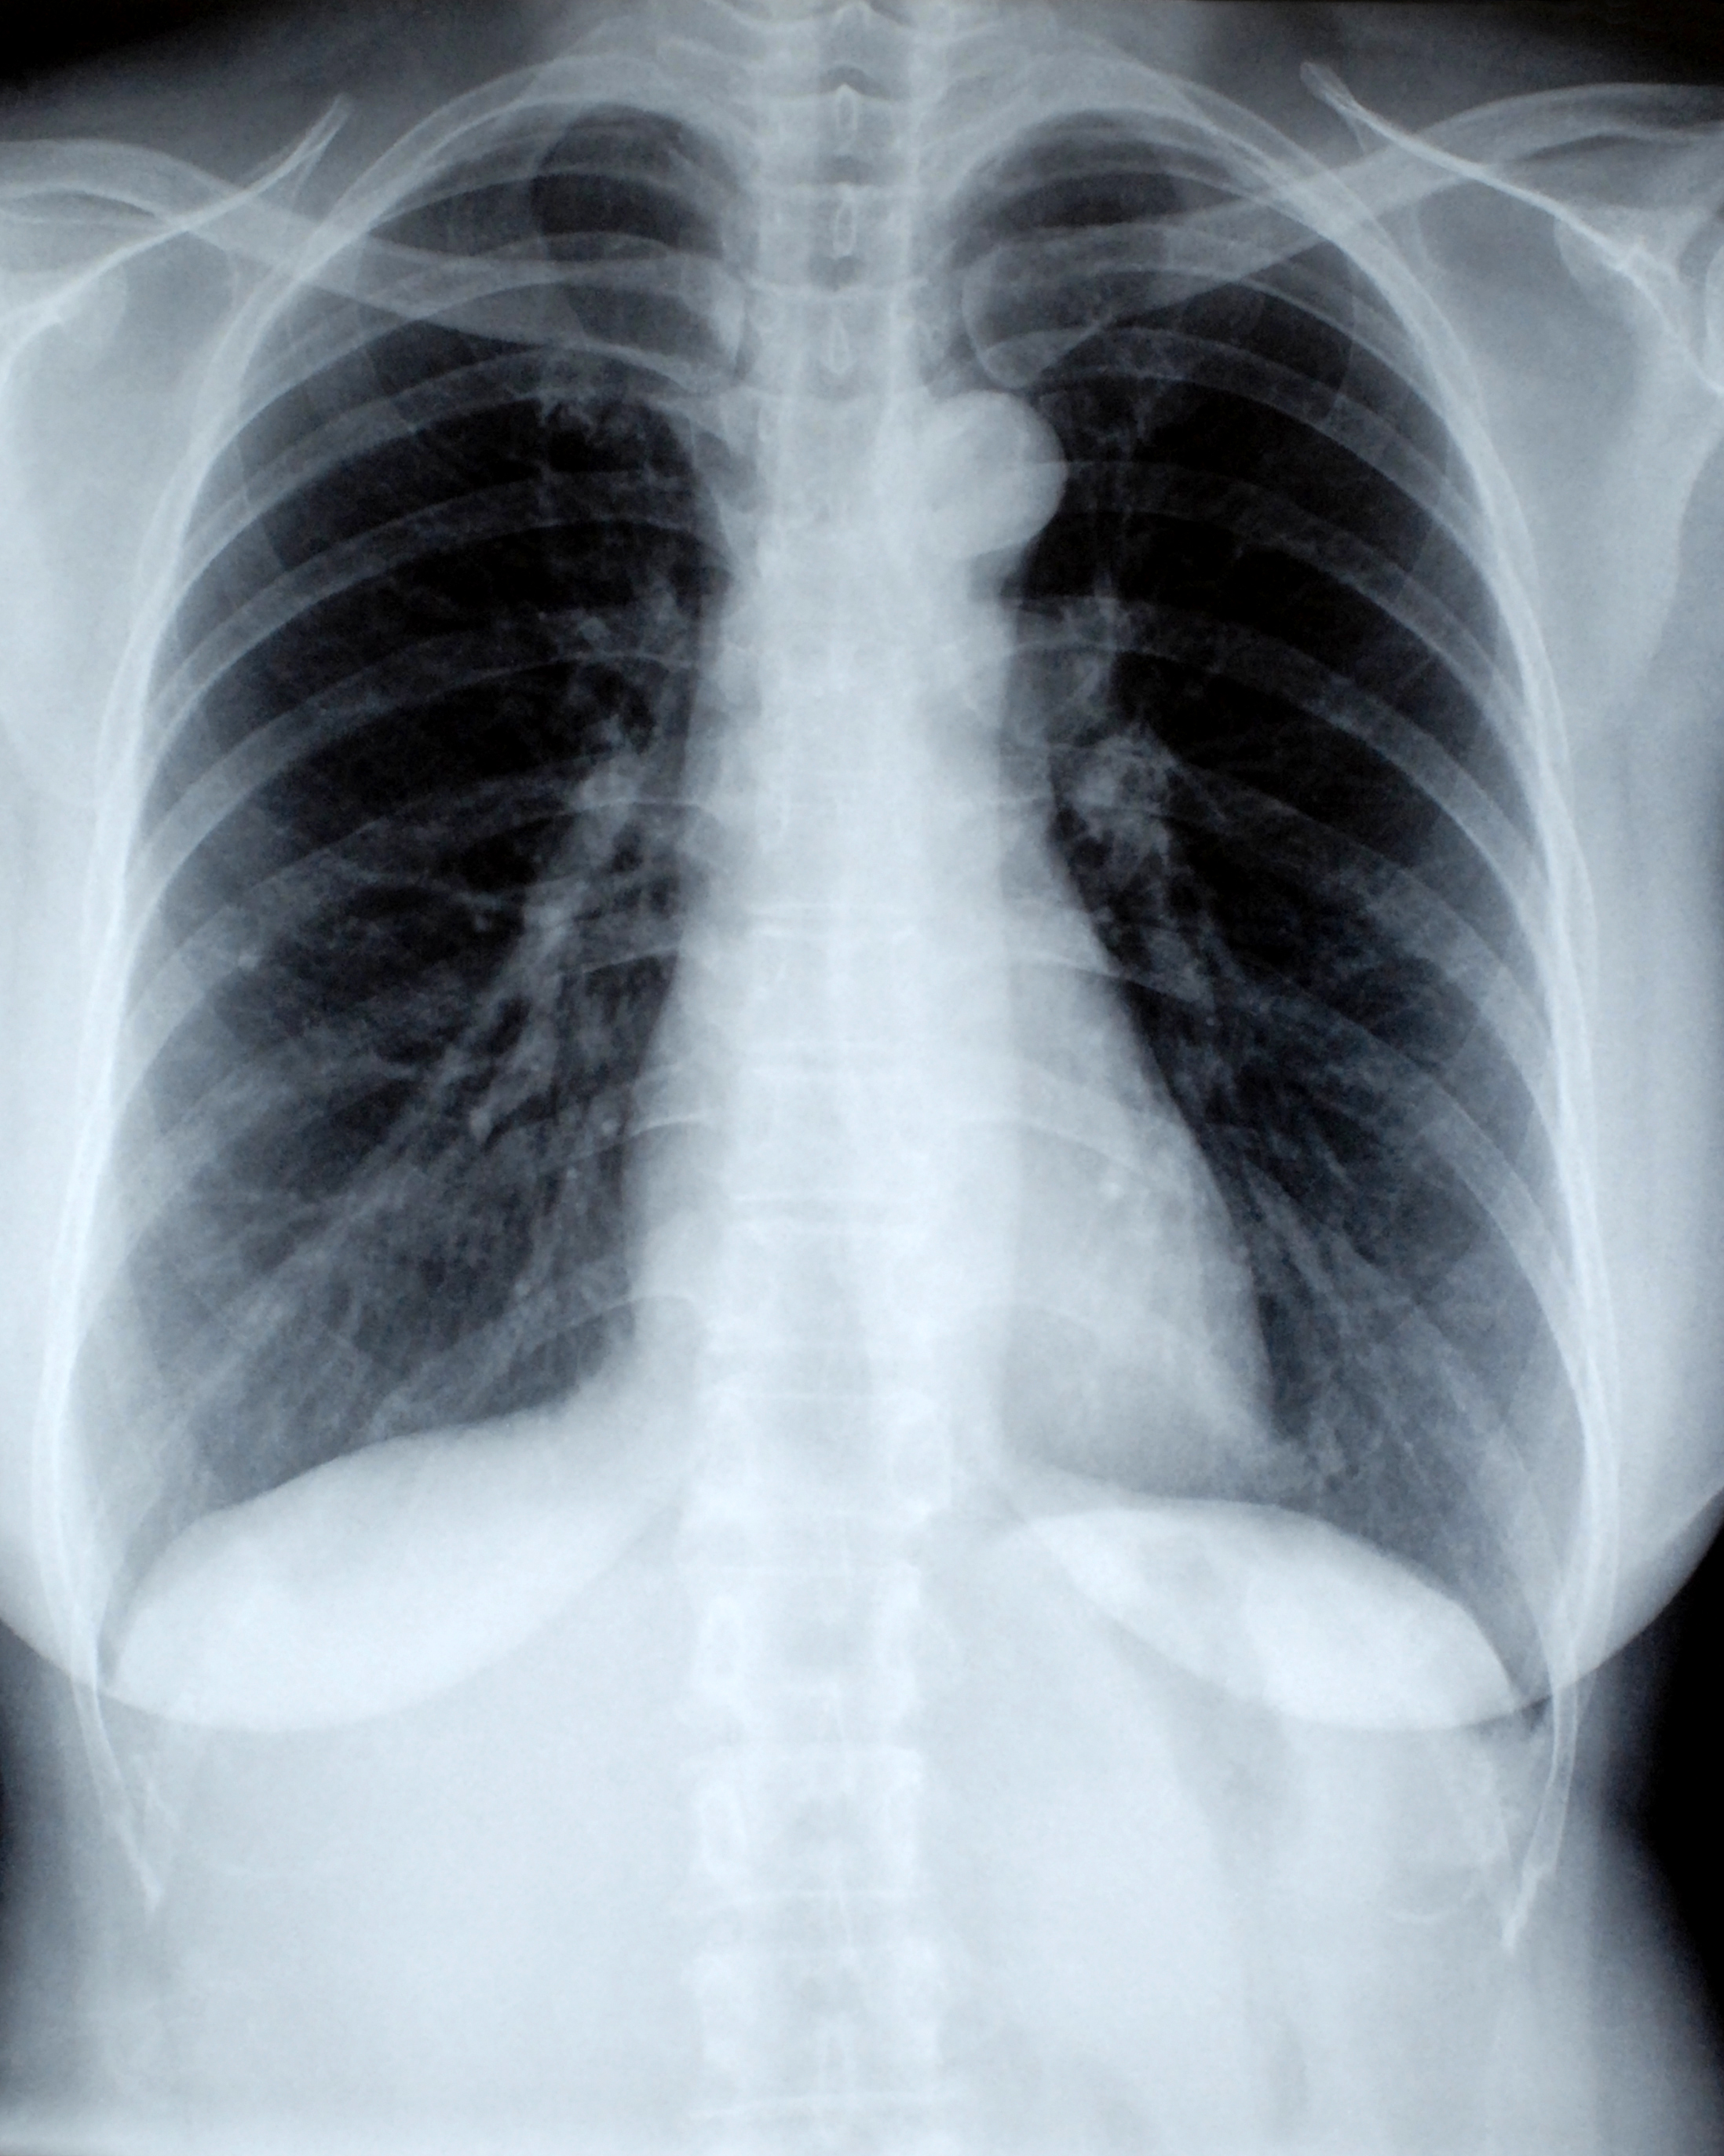

My research focuses on building trustworthy and explainable AI systems to support clinical decision-making through medical image analysis. I've developed and deployed deep learning models for COVID-19 chest X-ray classification, stock market trend prediction, and sentiment analysis — all designed to make AI more accessible and impactful.

A deep learning model to classify chest X-rays into COVID, Pneumonia, and Normal cases using CNNs.